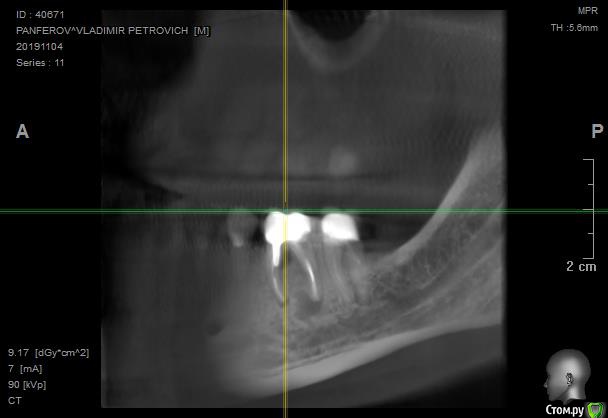

в 2011-м году 6-й снизу справа зуб был депульпирован, спустя несколько лет установлена коронка с ВКВ

Перед заменой коронки на соседнем зубе сделали контрольный снимок, обнаружили кисту.

Лечащий врач считает невозможным извлечь ВКВ. С учетом того, что зуб не беспокоит предложила сделать контрольный снимок через год и там принимать решение об удалении в зависимости от роста кисты.

Если мы рассуждаем о жизнеспособности данного (6-го) зуба, то его прогноз ухудшается наличием процесса между корнями в первую очередь, а кистой во вторую.

Уверен на 90%, что извлекая вкладку из данного зуба, ему можно подписать приговор на удаление.